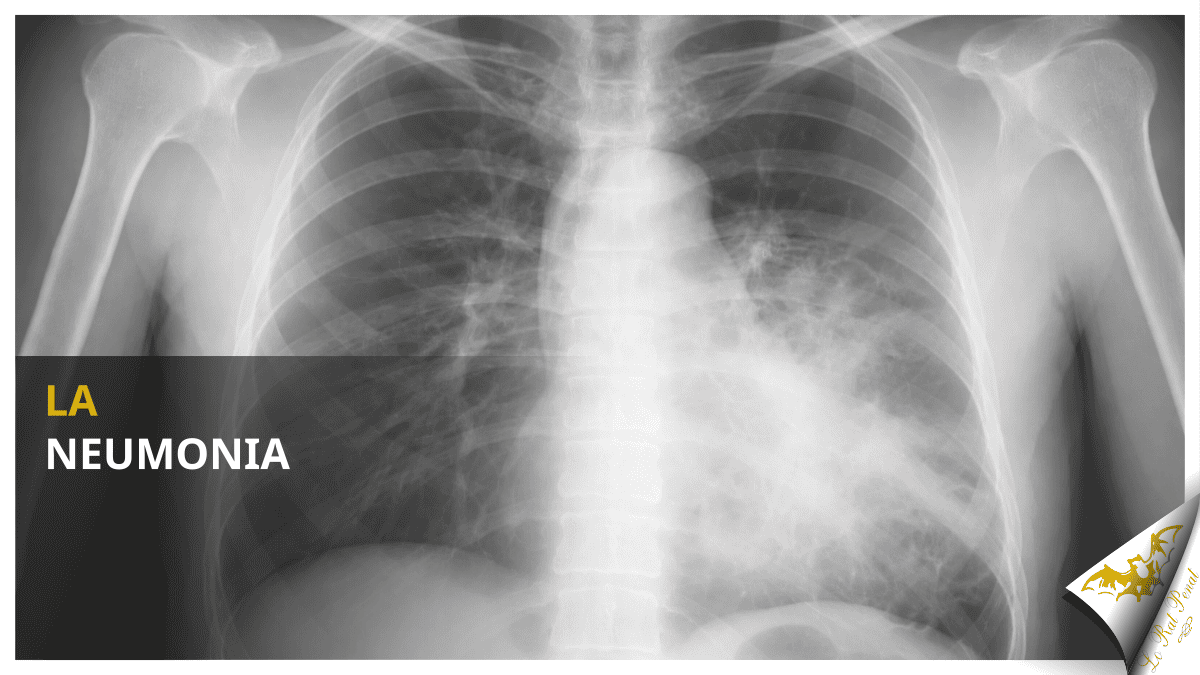

El diagnòstic d’una neumonia és clínic —reconeiximent dels síntomes— i radiològic. Per mig d’una radiografia de tórax se pot confirmar l’existència d’eixa ocupació d’alveols de la que parlàvem adés. No obstant açò, en situacions greus, s’utilisen proves més alvançades.